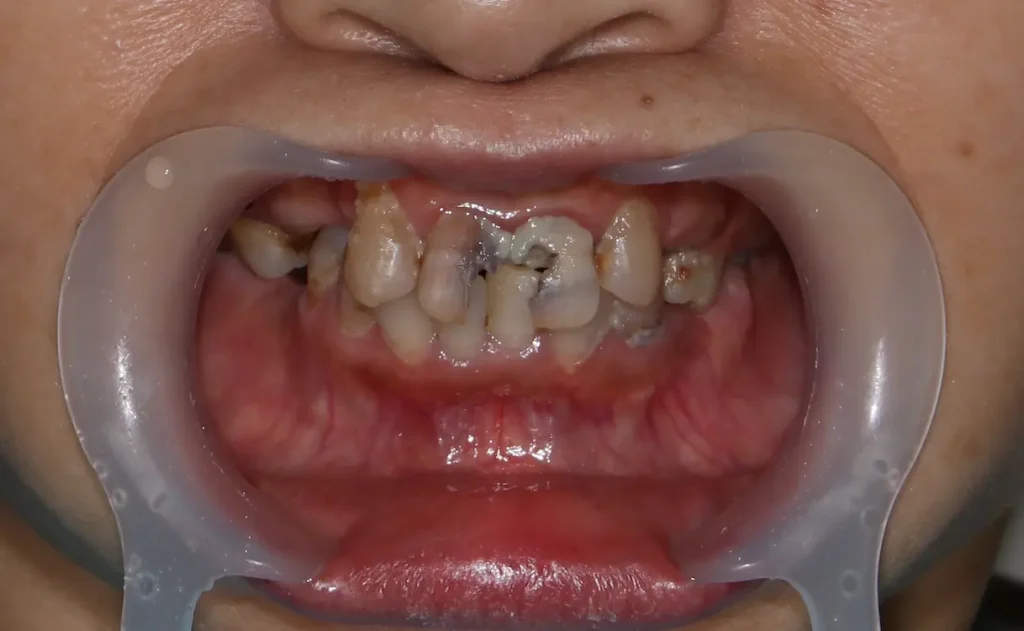

歯は噛み合う相手がなくなると、上の写真のように徐々に伸びてきます。

これを挺出(ていしゅつ)といいます。